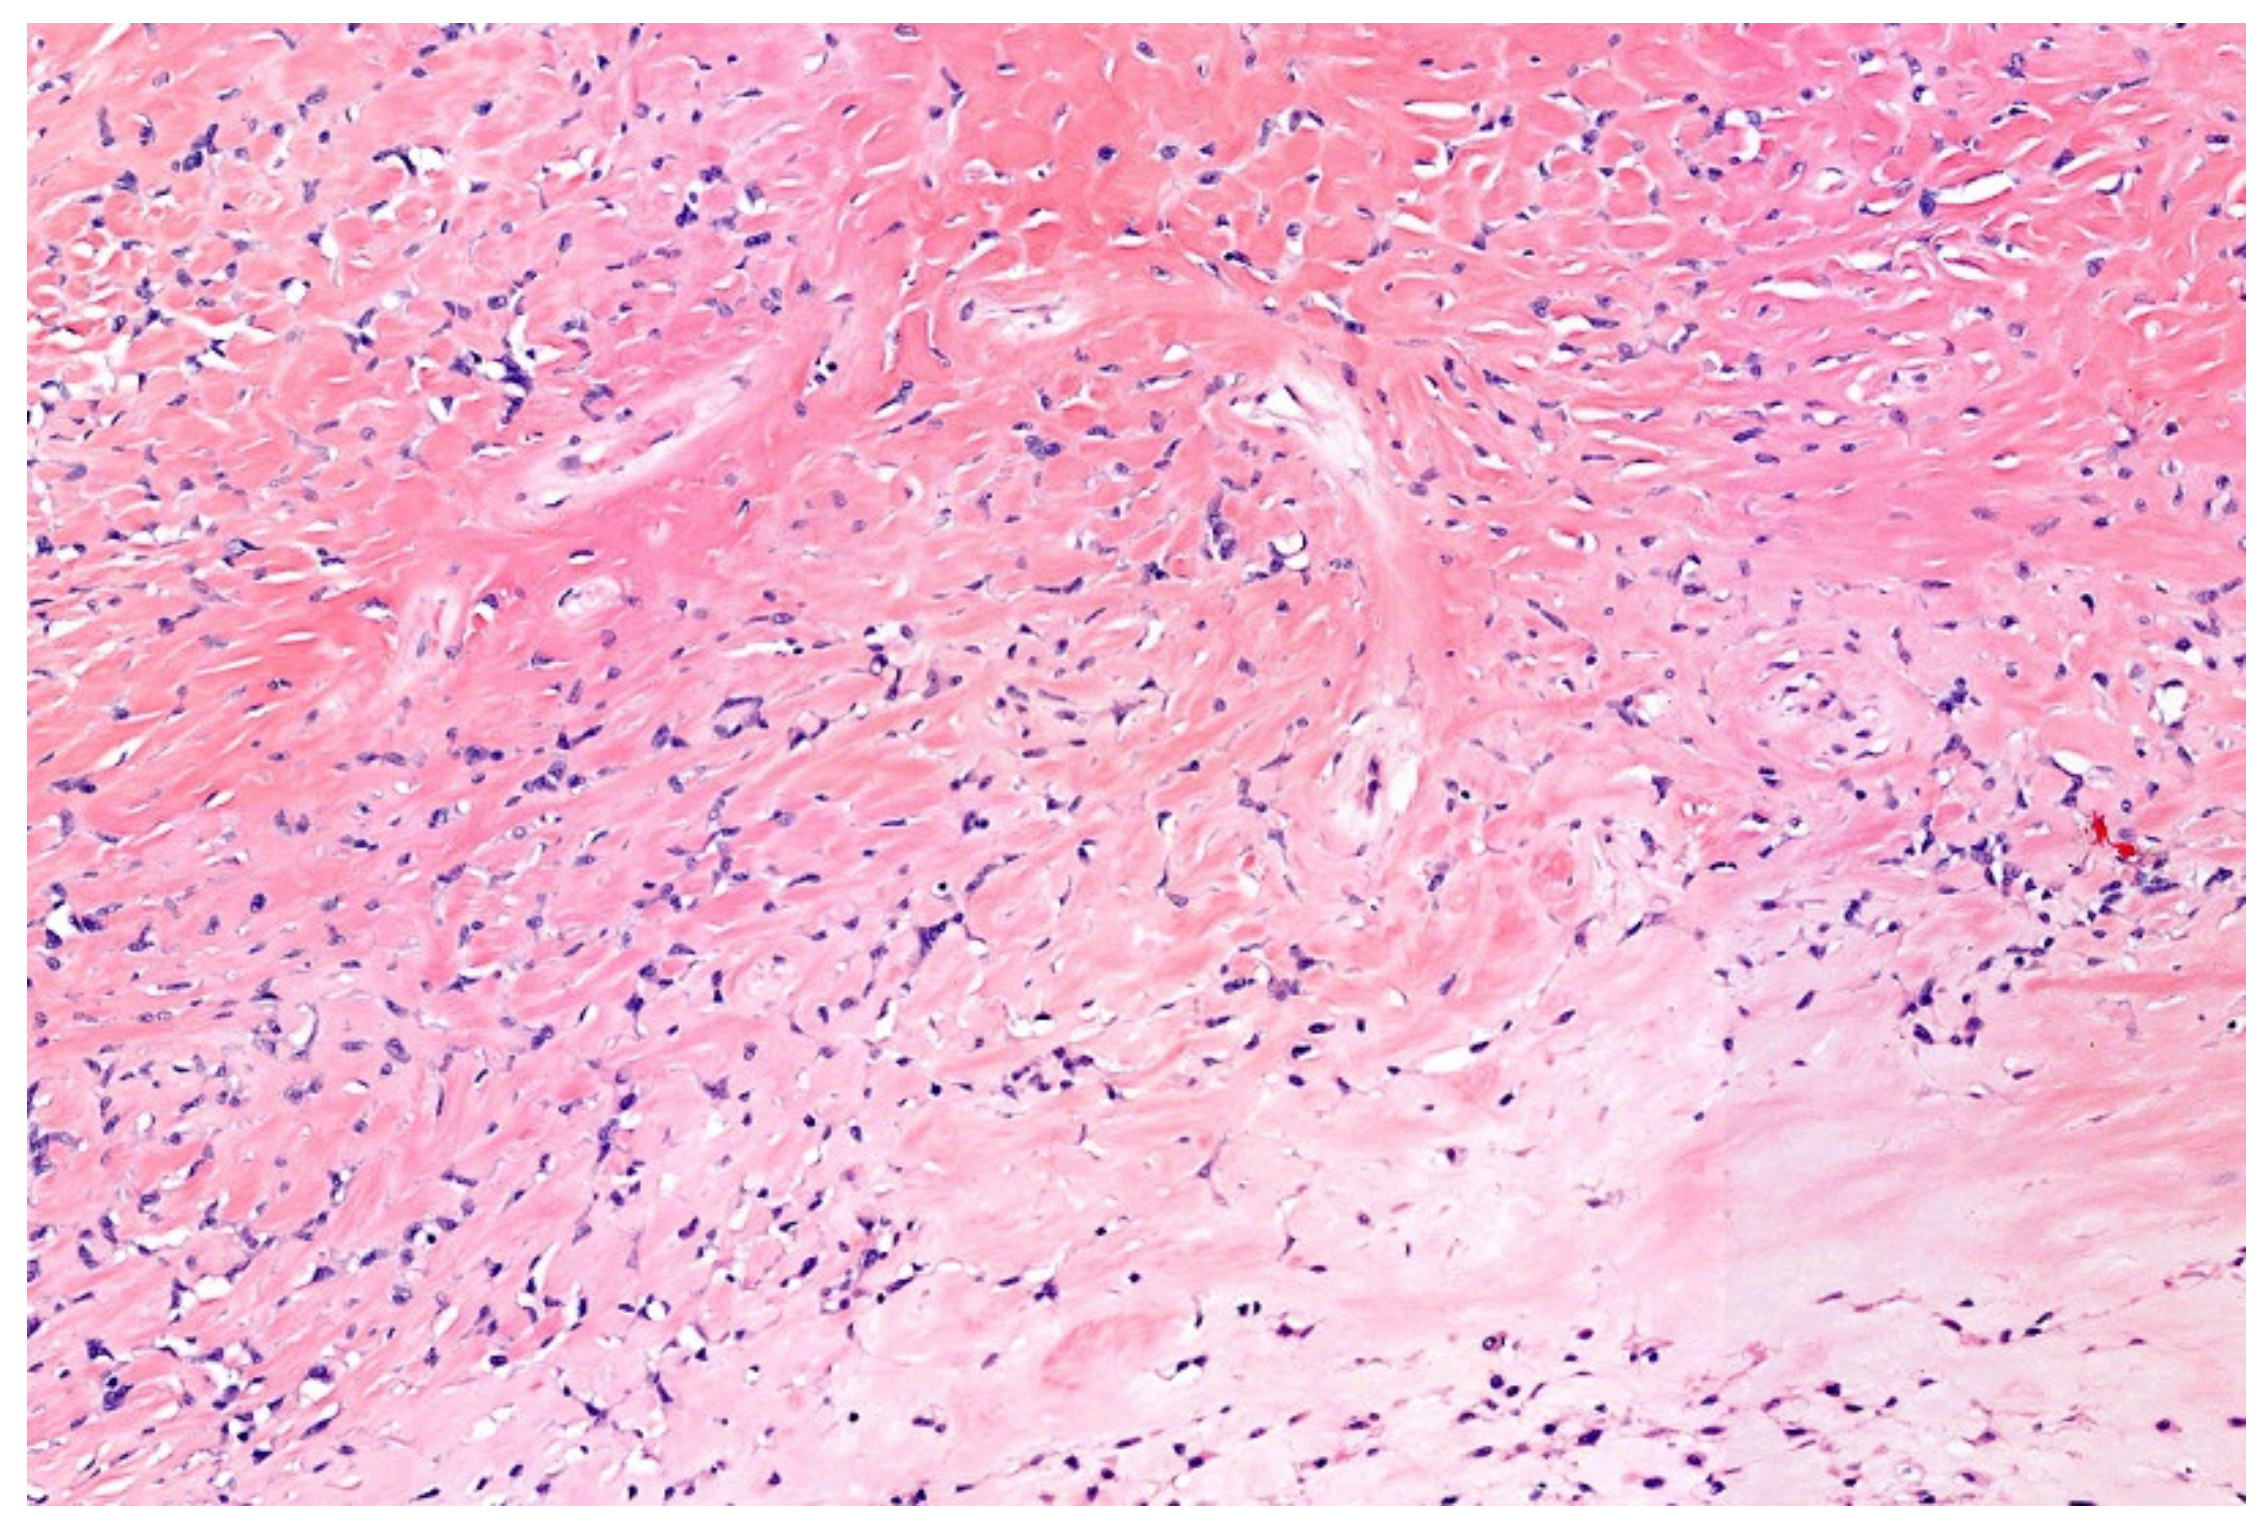

7. Low-Grade Fibromyxoid Sarcoma (LGFMS)/Sclerosing Epithelioid Fibrosarcoma (SEF)

- Guillou, L.; Benhattar, J.; Gengler, C.; Gallagher, G.; Ranchère-Vince, D.; Collin, F.; Terrier, P.; Terrier-Lacombe, M.J.; Leroux, A.; Marquès, B.; et al. Translocation-positive low-grade fibromyxoid sarcoma: Clinicopathologic and molecular analysis of a series expanding the morphologic spectrum and suggesting potential relationship to sclerosing epithelioid fibrosarcoma: A study from the French Sarcoma Group. Am. J. Surg. Pathol. 2007, 31, 1387–1402. [Google Scholar] [CrossRef] [PubMed]

- Evans, H.L. Low-grade fibromyxoid sarcoma. A report of two metastasizing neoplasms having a deceptively benign appearance. Am. J. Clin. Pathol. 1987, 88, 615–619. [Google Scholar] [CrossRef] [PubMed]

- Evans, H.L. Low-grade fibromyxoid sarcoma: A clinicopathologic study of 33 cases with long-term follow-up. Am. J. Surg. Pathol. 2011, 35, 1450–1462. [Google Scholar] [CrossRef] [PubMed]

- Evans, H.L. Low-grade fibromyxoid sarcoma. A report of 12 cases. Am. J. Surg. Pathol. 1993, 17, 595–600. [Google Scholar] [CrossRef]

- Doyle, L.A.; Möller, E.; Dal Cin, P.; Fletcher, C.D.; Mertens, F.; Hornick, J.L. MUC4 is a highly sensitive and specific marker for low-grade fibromyxoid sarcoma. Am. J. Surg. Pathol. 2011, 35, 733–741. [Google Scholar] [CrossRef]